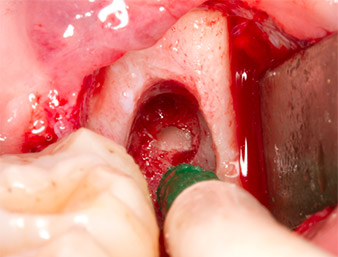

Nach Leitungs- und Lokalanästhesie wurde das Operationsfeld für einen bukkal-retromolaren Zugang weichgewebig eröffnet und dargestellt (Abb. 3).

Das Gewebe über dem Wurzelrest war nicht vollständig verknöchert und bestand zu einem großen Teil aus entzündlich verändertem Granulationsgewebe (Abb. 4).